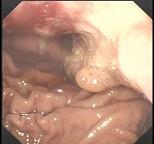

问题 患者,男性50岁,近2个月来出现中上腹隐痛,餐后更甚,伴早饱、厌食,乏力,无发热、黄疸,体重减轻了5Kg,大便隐血阳性,胃镜检查如图,则该患者最可能的诊断是 ( )

选项 A、胃癌 B、食管癌 C、消化性溃疡 D、胃溃疡出血 E、慢性胃炎

答案 A